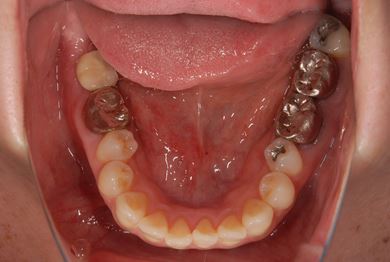

| 性別/年齢 | 女性 / 39歳 | ||||||||||||||||||||||||||||||||

| 主訴 | 右奥歯の虫歯と、右奥のインプラント治療について相談。 | ||||||||||||||||||||||||||||||||

| 治療方針 | 右下奥欠損部分をインプラント治療にて、機能的・審美的回復を行う。 | ||||||||||||||||||||||||||||||||

| 治療内容 | インプラント1本、ハイブリッドセラミッククラウン1本 | ||||||||||||||||||||||||||||||||